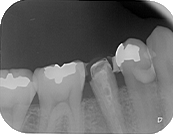

40代女性。左下第二小臼歯の歯根破折。力のかかりやすい臼歯部が失活歯となっており、歯根破折が認められる。この症例の場合、破折を起こした歯に被せ物が装着されていいない事も原因の可能性がある。

40代女性。左下第二小臼歯の歯根破折。力のかかりやすい臼歯部が失活歯となっており、歯根破折が認められる。この症例の場合、破折を起こした歯に被せ物が装着されていいない事も原因の可能性がある。